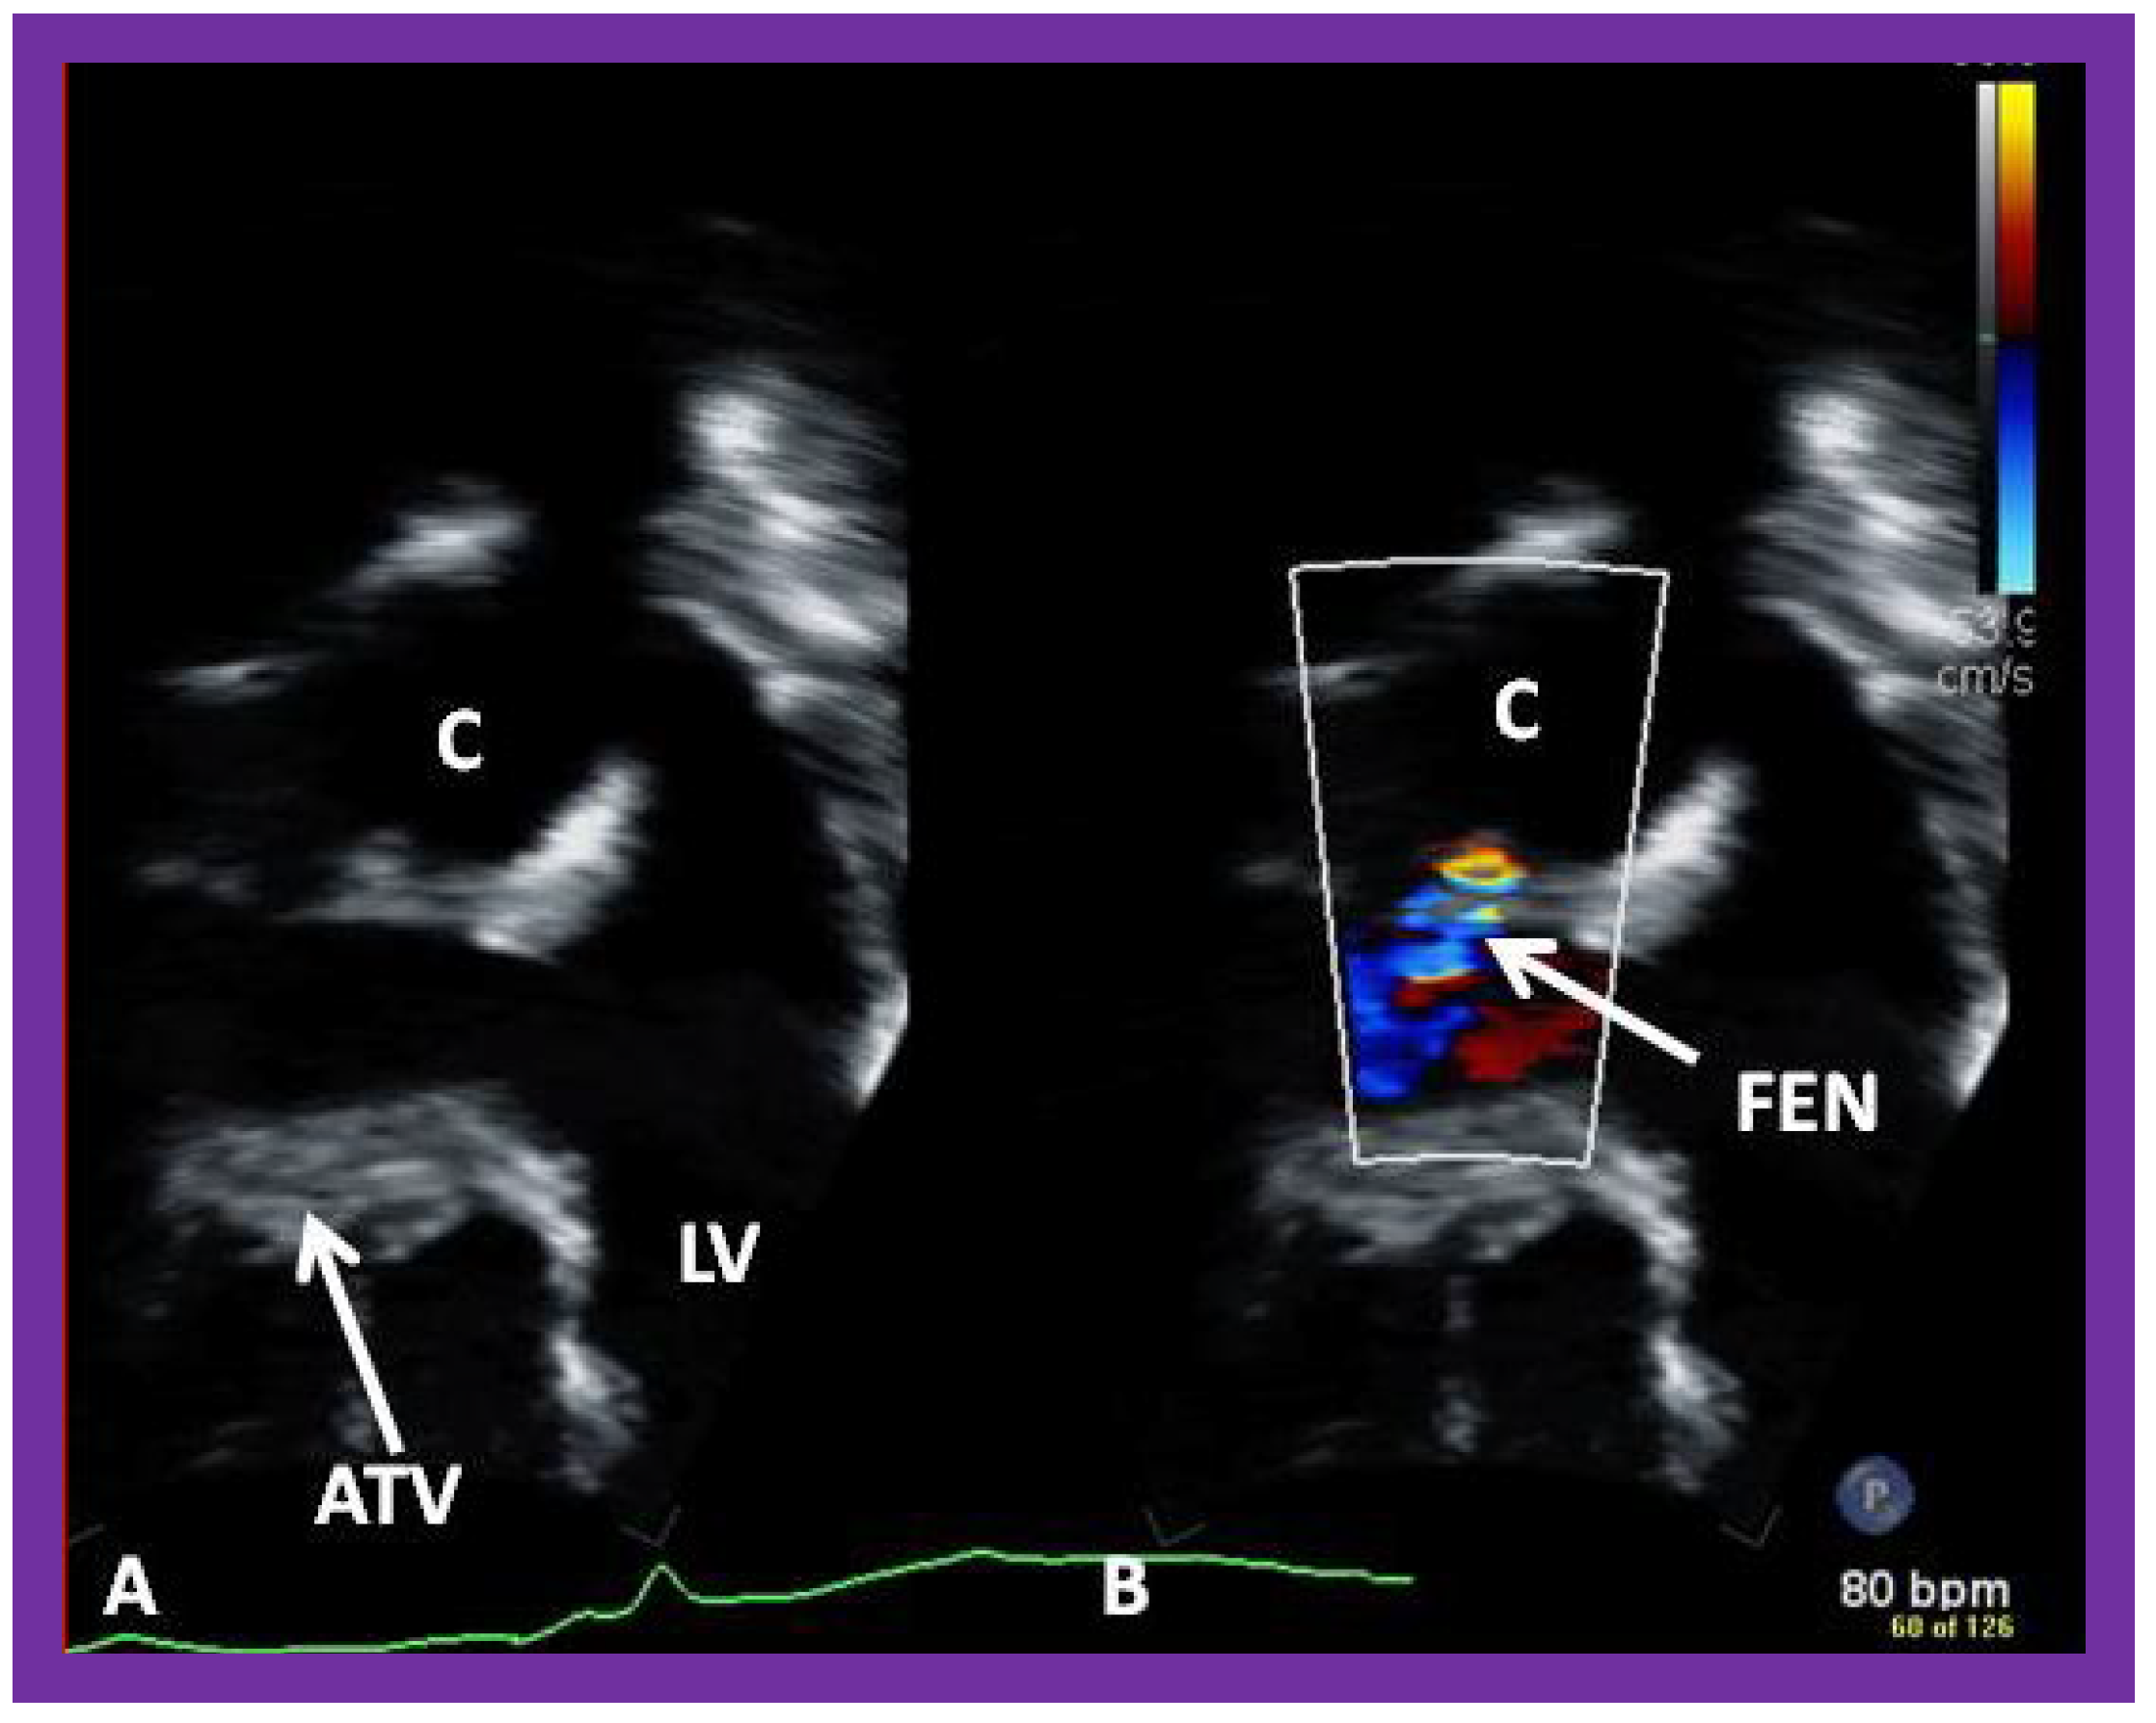

Figure 40. Selected video frames from apical four-chamber views demonstrating unobstructed pathway (UOP) (long arrow) between the right and left (LA) atria; the mitral valve is closed in (A) while it is open in (B). ATV, atretic tricuspid valve; C, conduit; HRV, hypoplastic right ventricle; LV, left ventricle.

Post-Fontan echocardiographic anatomy is best displayed in apical four chamber views, as demonstrated in Figure 38, Figure 39 and Figure 40. The remnants of the RA and the LA are seen (Figure 38, Figure 39 and Figure 40). The remnants of atrial septum are not usually seen since the atrial septum is completely removed either during bidirectional Glenn or Fontan surgery. Unobstructed pathway allowing emptying of blood flow from the coronary sinus and thebesian veins is usually seen in an apical four chamber view (Figure 40).